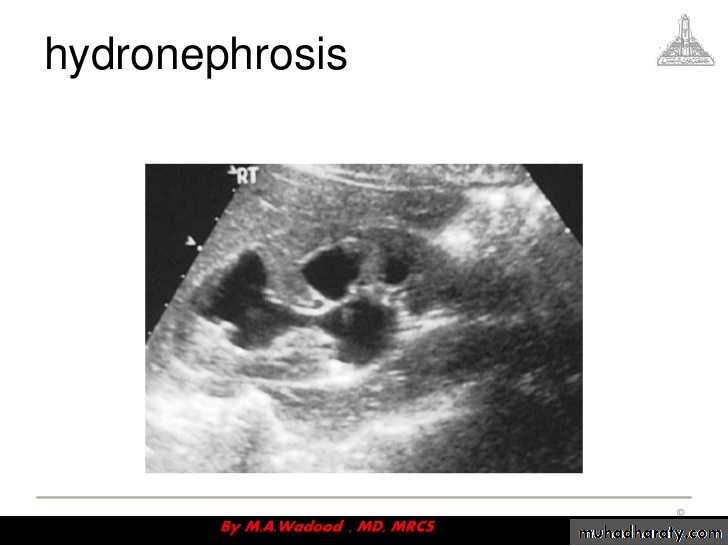

Renal colic

Renal colic- Management